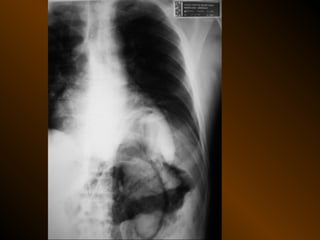

KHÍ TỰ DO

TRONG KHOANG PHÚC MẠC

NGUYÊN NHÂN

thủng tạng rỗng

nguồn gốc xuyên phúc mạc

nguồn gốc trong phúc mạc

10 – 15% thủng tạng rỗng → không thấy hơi tự do ổ bụng

KHÍ TỰ DO TRONGKHOANG PHÚC MẠC NGUYÊN NHÂN thủng tạng rỗng nguồn gốc xuyên phúc mạc nguồn gốc trong phúc mạc 10 – 15% thủng tạng rỗng → không thấy hơi tự do ổ bụng